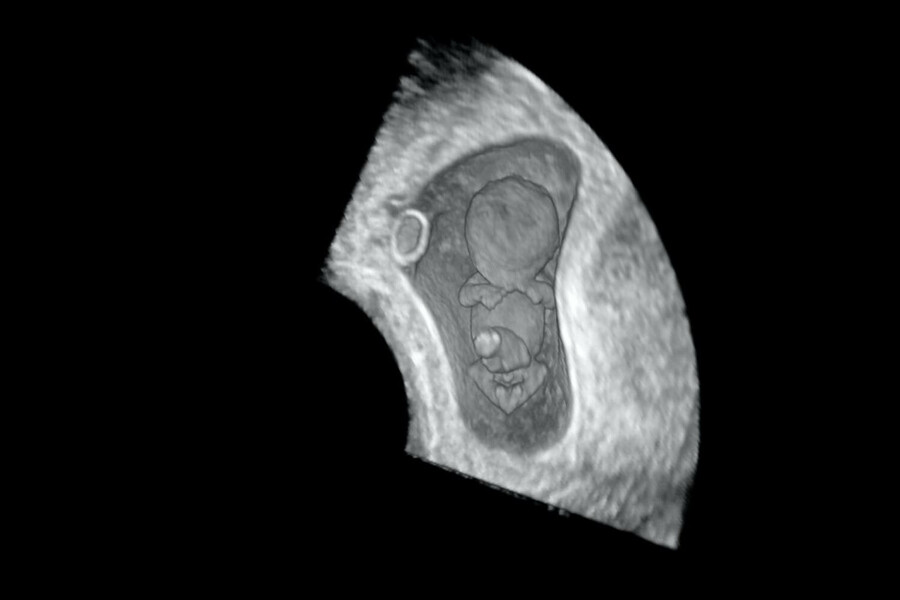

Ученые использовали современные технологии визуализации, в том числе 3D-УЗИ с трансвагинальными датчиками высокого разрешения и методы виртуальной реальности для создания 3D-моделей эмбриона. Это позволило им оценить общее развитие эмбриона. Всего они проанализировали 611 удачных беременностей и 33 беременности, которые закончились выкидышем.